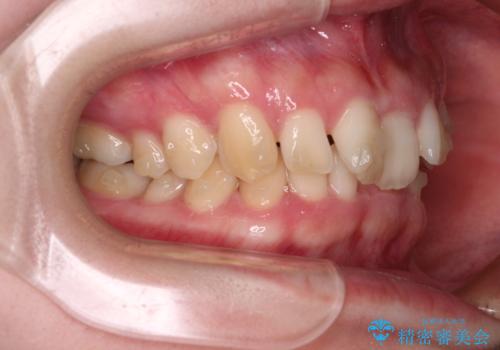

奥歯の咬み合わせを見ると、片方は上顎が下顎に対して相対的に前方にあり、他方は交叉した咬合の状態でした。

咬み合わせを改善するためには、上顎臼歯を後方に移動させた咬み合わせにする必要があります。

インビザライン単体で改善することも可能ですが、ディープバイトのためインビザライン単体で達成する可能性が低いと考えられたため、カリエール・ディスタライザーという補助装置を併用して、より確実性を上げることとしました。

カリエール・ディスタライザーを使用している期間、反対側はワイヤー矯正により叢生を解消していくこととしました。

奥歯の咬み合わせを改善しながら、並行してインビザラインで歯列を整えることとしました。

カリエールディスタライザーやワイヤー矯正を併用したことで、確実かつ短期間で治療を終えることができました。